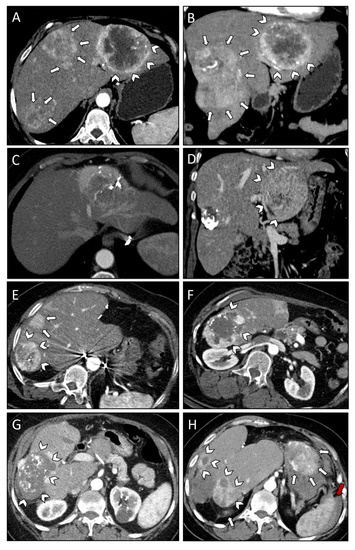

| Case #2 | Treatment | Comments | Liver Segments | Classification | Complications |

| 16.06.2015 | TAE | Embozene™ Microspheres (500 μm), Soft Embolization Coils (Boston Scientific), Pushable Fibered and Detachable Non-Fibered Microcoils (Cook Medical) | VII, VIII, II, III | Initial | none |

| 31.07.2015 | TAE | Embozene™ Microspheres (2 × 100 μm, 4 × 250 μm, 1 × 750 μm) | VII, VIII | Initial | Infection of necrotic liver tissue (CD II) |

| 22.09.2015 | TAE | Embozene™ Microspheres (4 × 100 μm, 2 × 250 μm, 2 × 400 μm) | V, VIII | Initial | Infection of necrotic liver tissue (CD II) |

| 01.12.2015 | Surgery | Right hemihepatectomy | V-VIII | Local recurrence | none |

| 15.02.2016 | SRFA + liver packing | 3 lesions, 3 cm max. diameter, 6 needles, 17 min ablation time | II | New lesions | none |

| 10.11.2016 | Surgery | 2 lesions, Resection S II + III, 6 h 47 min | II, III | Local recurrence | none |

| 16.03.2017 | SRFA | 1 lesion, 2 cm max. diameter, 3 needles, 6 min ablation time | IVa | New lesion | none |

| 11.08.2017 | SRFA | 3 lesions, 0.8 cm max. diameter, 5 needles, 12 min ablation time | IVa | New lesions | none |

| 01.02.2018 | SRFA | 2 lesions, 1 cm max. diameter, 2 needles, 8 min ablation time | IVb | New lesions | none |

| 11.19–01.20 | Systemic therapy | Axitinib | New lesions, local recurrence | Progressive disease under therapy axitinib (new intracranial tumor 01/20) | |

| 09.06.2020 | Systemic therapy | Temozolomide, bevacizumab | New lesions | Progressive disease under therapy | |